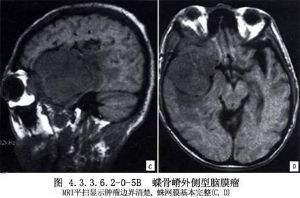

内侧型:起源于前床突与小翼内侧,肿瘤多为球形,毗邻为视神经、嗅神经、视交叉、眶上裂、颈内动脉的床突上段、分叉部、大脑中动脉和大脑前动脉的水平段、后交通动脉与海绵窦。有时肿瘤破坏眶上裂,向眼眶内生长,引起眼球突出和视力障碍。肿瘤向鞍上区及后上发展时,尚可引起垂体-下丘脑功能障碍。(图4.3.3.6.2-0-5A~C,4.3.3.6.2-0-6A~C)